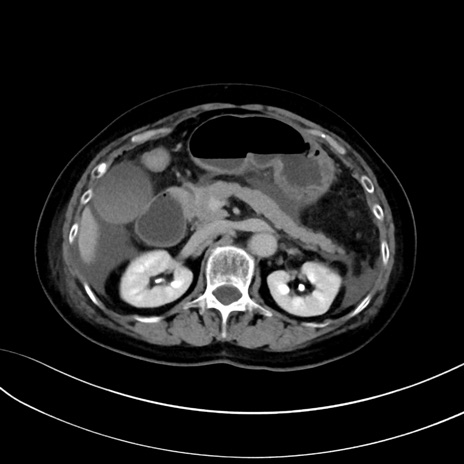

症例13 CT(横断像)1日半後